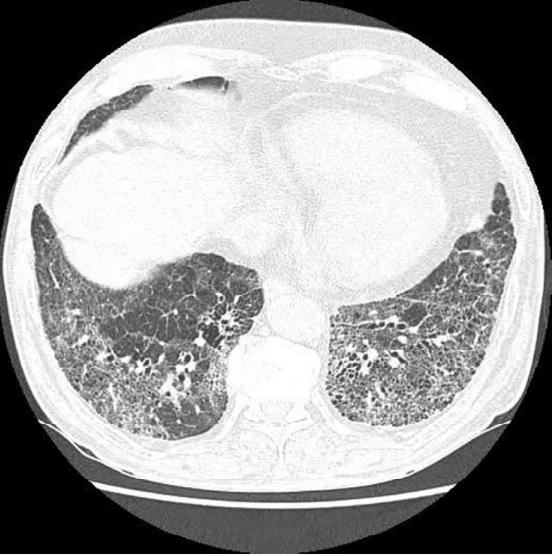

45세 남자가 6개월 전부터 기침이 심해지고 숨이 차서 병원에 왔다. 자동차 도장공으로 15년째 근무 중이고 비흡연자이다. 혈압 120/80 mmHg, 맥박 90/분, 호흡 20회/분, 체온 36.4°C이다. 가슴 X선사진과 가슴 컴퓨터단층촬영 사진이다. 검사 결과는 다음과 같다. 진단은?

CT: Bilateral basal reticular opacities

• CXR상 bilateral diffuse opacities가 관찰되며 chest CT상 양쪽 bilateral basal area에 fibrotic change를 시사하는 reticular opacities가 확인된다. 더불어 PFT상 제한성 양상으로, 영상소견과 폐기능 검사 소견을 종합하여 판단할 때 증상의 원인이 간질성 폐질환임을 알 수 있다.

• 간질성 폐질환 중 유기 화합물을 지속적으로 흡입하는 환자의 직업력을 고려하였을 때 가장 유력한 진단은 과민폐렴이며, 환자의 chest CT 소견 역시 이에 부합한다.

• 과민성 폐렴의 HRCT 소견

비섬유성

섬유성

• Diffuse GGO

• Mosaic attenuation

• Expiratory air trapping

• Reticular opacities

• Traction bronchiectasis

• Subpleural honeycombing